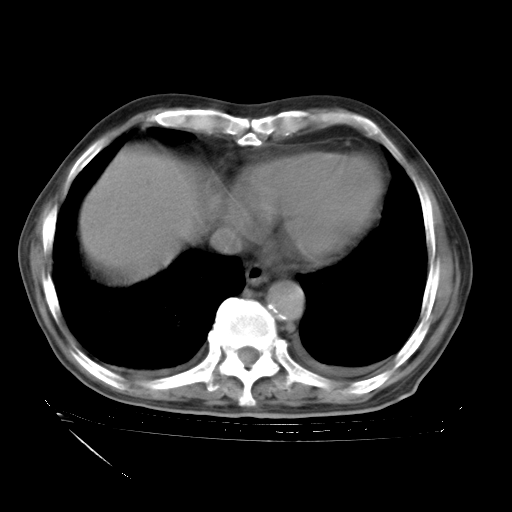

经过24天治疗,岳父的病情基本稳定。生活基本可以自理,可以下床活动。呼吸困难早已消失。体温基本正常。

只是甲强龙用80mg时血小板升到正常,改为60mg后又降到63×10*9/L。

主要治疗甲强龙80mg×14天,60mg×10天;同时抗结核(异烟肼+利福平+乙胺丁醇)。环磷酰胺0.1 tid 10天。

特别感谢胡教授、高管、桃子版主给出关键的治疗建议。桃版把所有肺部影像和全部临床资料请所在医院呼吸科、感染病科、结核科、临床免疫科专家会诊。临床免疫科专家制定了完整的治疗方案。

下一步治疗强地松+环磷酰胺+抗结核。 |